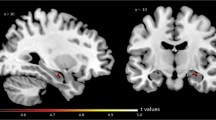

Association of global Aβ deposition and regional synaptic density in aMCI and dementia

The primary analysis investigated the association of global Aβ deposition and hippocampal synaptic density (SV2A binding; Fig. 2). We hypothesized that in participants with aMCI (a stage of continued Aβ accumulation) but not in those with dementia (a stage of relative Aβ plateau), global Aβ deposition would be inversely associated with synaptic density in the hippocampus. Separate univariate linear regressions for aMCI and dementia groups demonstrated a significant inverse association in participants with aMCI (r = − 0.55, P = 0.04) but not in those with dementia (r = 0.05, P = 0.82). This difference between group correlation coefficients was significant (Fisher z = − 1.80, one-tailed P = 0.04). Addition of age and sex as covariates to this model reduced the previously observed significance in the aMCI group (R2 = 0.36, semi-partial correlation coefficient = − 0.48, P = 0.09), while the association between global Aβ deposition and hippocampal SV2A in the dementia group remained non-significant (R2 = 0.24, semi-partial correlation coefficient = 0.07, P = 0.72). When participants from the aMCI and dementia groups were pooled (n = 38), the inverse association between global Aβ and hippocampal SV2A was not significant (Pearson r = − 0.24, P = 0.58). Secondary exploratory analyses across multiple ROIs suggested no broad associations between global Aβ deposition and regional SV2A in either diagnostic group (Table 2). However, a nominal inverse association was observed between global Aβ deposition and lateral parietal SV2A in the dementia group (r = − 0.43, P = 0.03).

Correlation of global Aβ deposition and hippocampal SV2A in aMCI and dementia due to AD. Scatter plot with best-fit lines depicts a significant inverse association between global Aβ deposition and hippocampal SV2A in participants with aMCI (green) but not with dementia (red). Correlation coefficients were calculated from separate univariate linear regression analyses in each group with associated two-tailed P values, without correction for multiple comparisons. Global Aβ deposition was calculated by averaging values of [11C] PiB DVR from the bilateral prefrontal, lateral temporal, posterior cingulate/precuneus, and lateral parietal ROIs, weighted by volume. Green circles denote DVR values for aMCI participants, while red circles denote DVR values for participants with dementia. Abbreviations: DVR, distribution volume ratio using a whole cerebellum reference region; aMCI: amnestic mild cognitive impairment; SV2A, synaptic vesicle glycoprotein 2A; PiB, Pittsburgh Compound B

Correction for partial volume effects revealed similar results to those observed in non-corrected data across all correlational analyses, including associations between global Aβ deposition and hippocampal SV2A binding (Supplementary Figure 4), global Aβ deposition and SV2A binding in neocortical ROIs (Supplementary Table 4), and global Aβ deposition and regional SV2A binding in all FreeSurfer regions (Supplementary Figure 5).

In this study, we investigated the association of cerebral Aβ deposition using [11C] PiB and regional synaptic density using [11C]UCB-J. Overall, our analyses were consistent with previous research showing that Aβ plaque burden is not well-correlated with indices of clinical severity. However, consistent with our hypothesis, we observed that in participants with aMCI (a stage of continued Aβ accumulation), global Aβ deposition was more strongly inversely associated with synaptic density in the hippocampus compared to those with dementia (a stage of relative Aβ plateau). This stronger association survived PVC (Supplementary Figure 4) and thus is not driven primarily by atrophy. Secondary exploratory analyses across multiple ROIs and whole brain analyses suggested no broad or consistent associations between global Aβ deposition and regional SV2A in either diagnostic group. The nominal negative associations with right-sided subcortical structures in aMCI but right-sided cortical regions with dementia participants (Fig. 3) in the full FreeSurfer region set are not fully mirrored in the corresponding surface-based analyses (Supplementary Figure 3) and may lack biological plausibility.